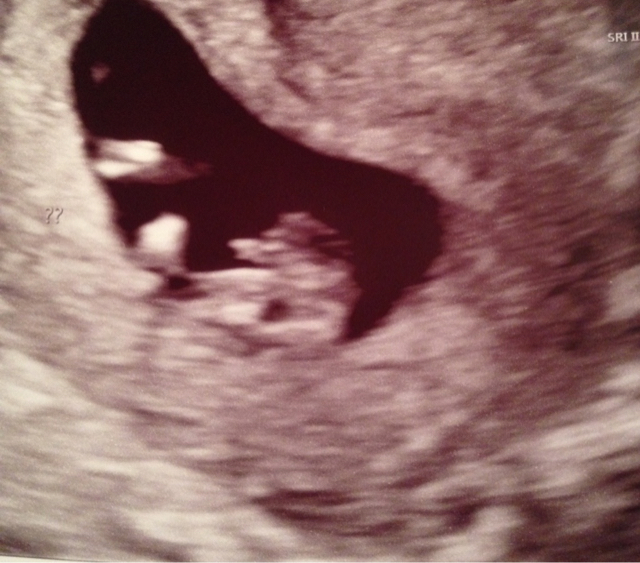

Lauren-we pretty much found out yesterday that baby is a boy. I know it's still early and people say it's too early to tell for sure, but the sono tech was very convinced it was a boy. There is no doubt when I look at the pics that it is a boy. Here are my potty and nub shots. Attachment 33393Attachment 33394

The difference I noticed between mine and yours is the bright white spot/bulge on mine that looks like it is going to end up being the scrotum[emoji17]

Looks boyish jdd, but I'm not 100% sure.

I would guess boy

Boy